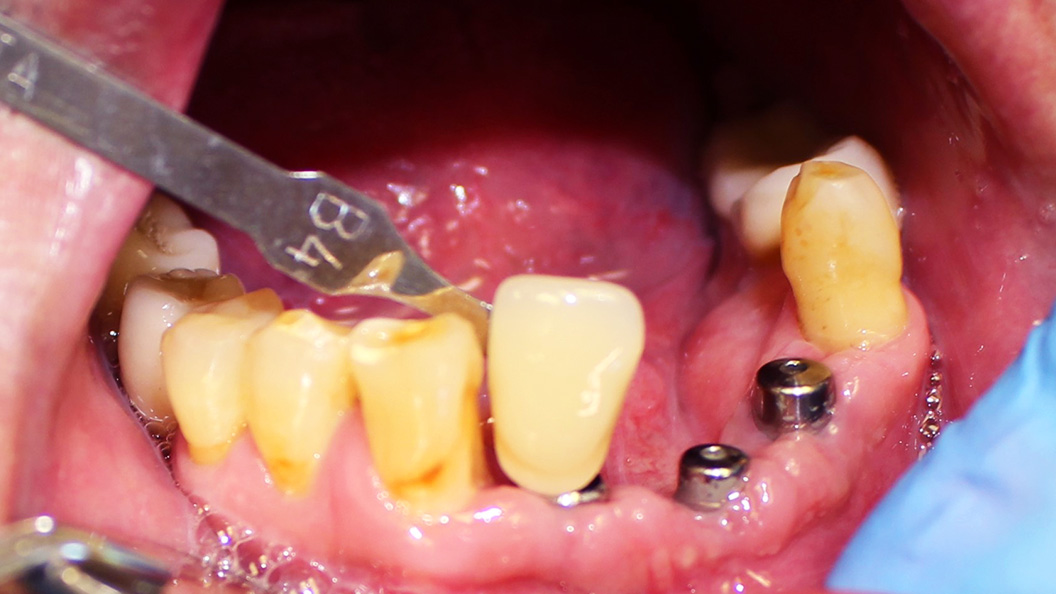

К нам в клинику обратился пациент с жалобой на частично отсутствующие зубы на нижней челюсти.

После осмотра и предварительной диагностики врач Мельников Алексей Владимирович рекомендовал провести имплантацию с последующим протезированием металлокерамическими конструкциями. После согласования плана лечения с пациентом приступили к лечению.

- установка 3 имплантов системы Alpha Bio;

- изготовление и установка металлокерамических коронок на имлантах системы Alpha Bio.